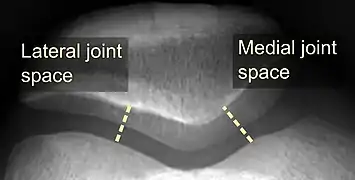

On X-ray, with skyline projections, dislocations are readily diagnosed. In borderline cases of subluxation, the following measurements can be helpful:

• The lateral patellofemoral angle, formed by:[16]

• A line connecting the most anterior points of the medial and lateral facets of the trochlea.

• A tangent to the lateral facet of the patella.

With the knee in 20° flexed, this angle should normally open laterally.[16]

• The patellofemoral index is the ratio between the thickness of the medial joint space and the lateral joint space (L). With the knee 20° flexed, it should measure 1.6 or less.[16]